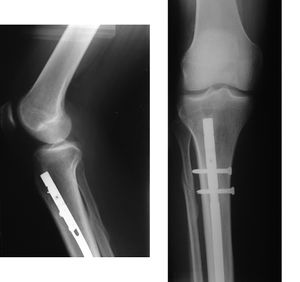

المسمار النخاعي intramedullary rod، هو مسمار معدني يزرع في تجويف نخاع العظام. ويستخدم المسمار النخاعي لعلاج كسور العظام الطويلة في الجسم. استخدمه لأول مرة گرهارد كنتشر عام 1939,[1][2] أثناء الحرب العالمية الثانية، لعلاج الجنود المصابين بكسر في عظمة الفخذ.